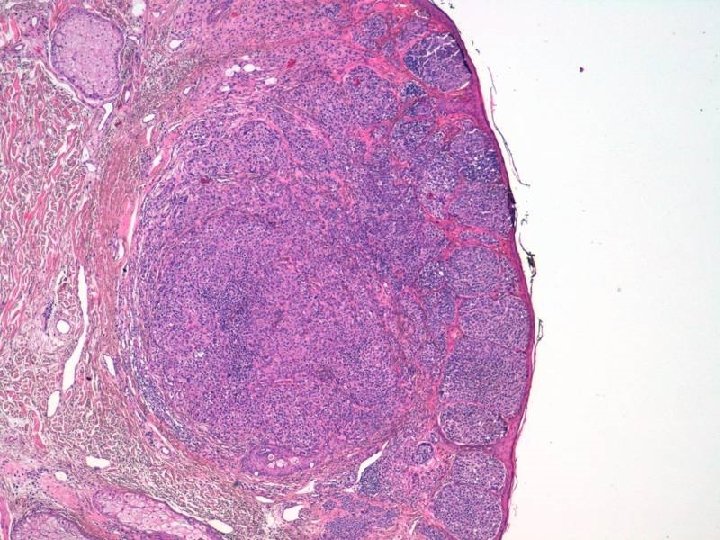

Examen Macroscópico Biopsia escisional Fragmento de piel de 1, 5 x 0, 8 x 0, 5 cms con lesión excrecente de color pardo claro de bordes irregulares, de 0, 5 x 0, 5 cm. Márgenes quirúrgicos libres a 1 mm del más cercano.

DIAGNOSTICO Melanoma dérmico originado sobre nevus melanocítico preexistente Tipo Miescher, no ulcerado, Nivel 4 de Clark, breslow de 1, 92 mms.

En el presente caso se observa la particularidad de que el componente de nevus se localiza lateralmente al melanoma y en continuidad con éste.